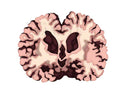

The cell of the brain died, and withered.

脳の細胞が死んでしまって萎縮した脳。徐々に進行する認知症